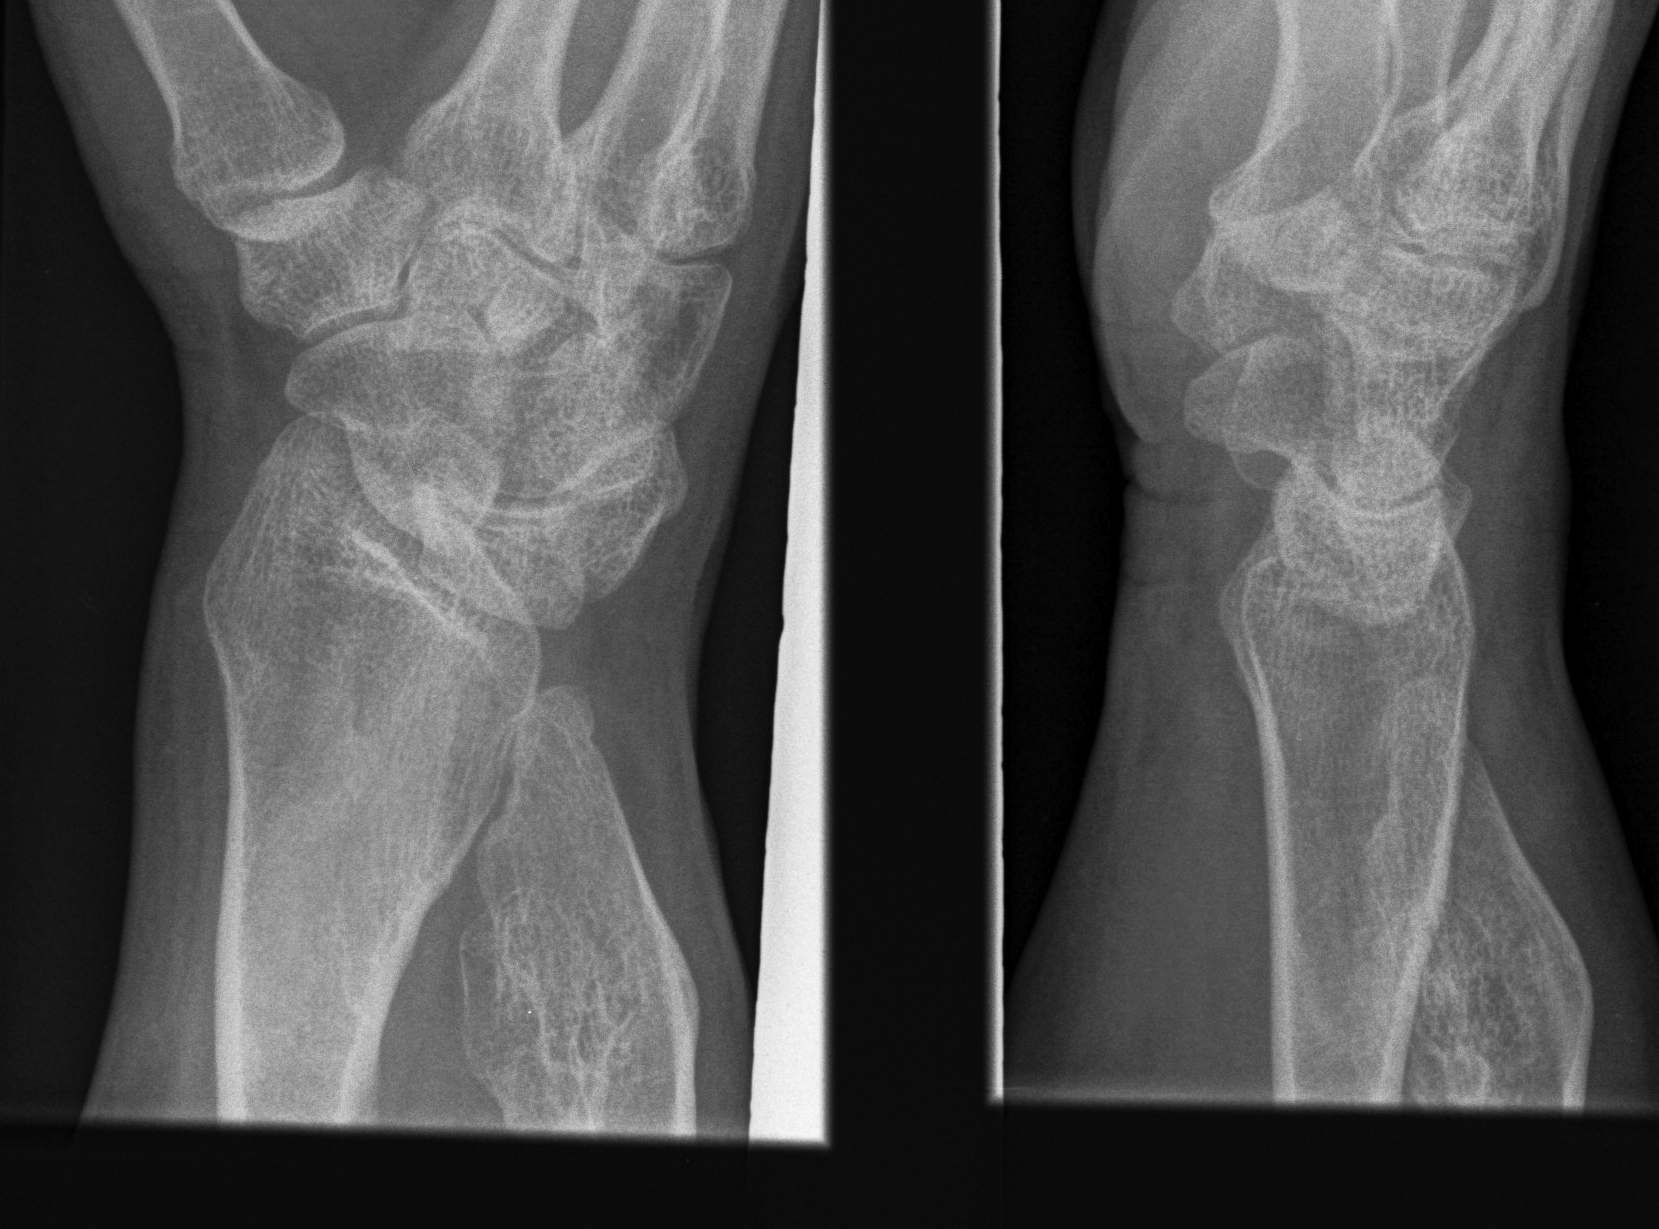

Forearm

- ulnar shortening / radial bowing / ulnar deviation of wrist

- can get radial head dislocation / carpal slip

Osteochondromas WristOsteochondromas Wrist LateralMulti OC wrist